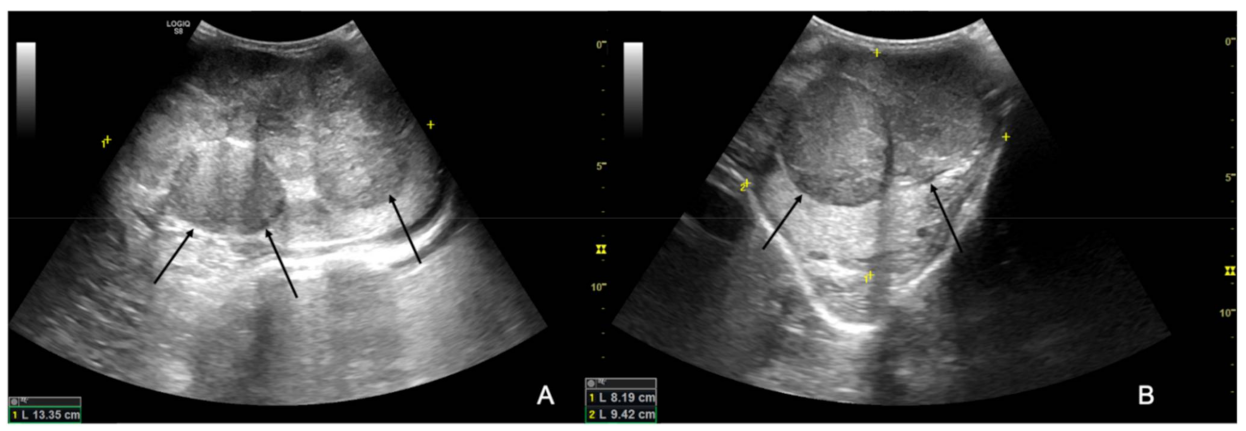

The ultrasound examination showed that the right testicle appeared normal (Figure 2), while the left testicle severely enlarged (13.35 cm CrCd × 8.19 cm DV × 9.42 cm LL vs. 9.25 cm CrCd × 4.75 cm DV × 6.91 cm LL). The parenchyma was characterized by the presence of multiple coalescing, nodular, well-defined and heterogeneous lesions of various size that almost completely effaced the normal anatomy and deformed the capsule or distorted normal shape (Figure 3); color Doppler and B-Flow evidenced a diffuse increase in vascularization, characterized by vessels of different size and localized both peripherally and in the central portion of the various nodular lesions, instead of normal unform vessel distribution from the capsule to the testicle mediastinum (Figure 4).

Figure 3. B-mode longitudinal (A) and transverse (B) images of the left testicle; the black arrows point at the heterogeneous and well-defined nodular lesions effacing the normal testicular parenchyma.